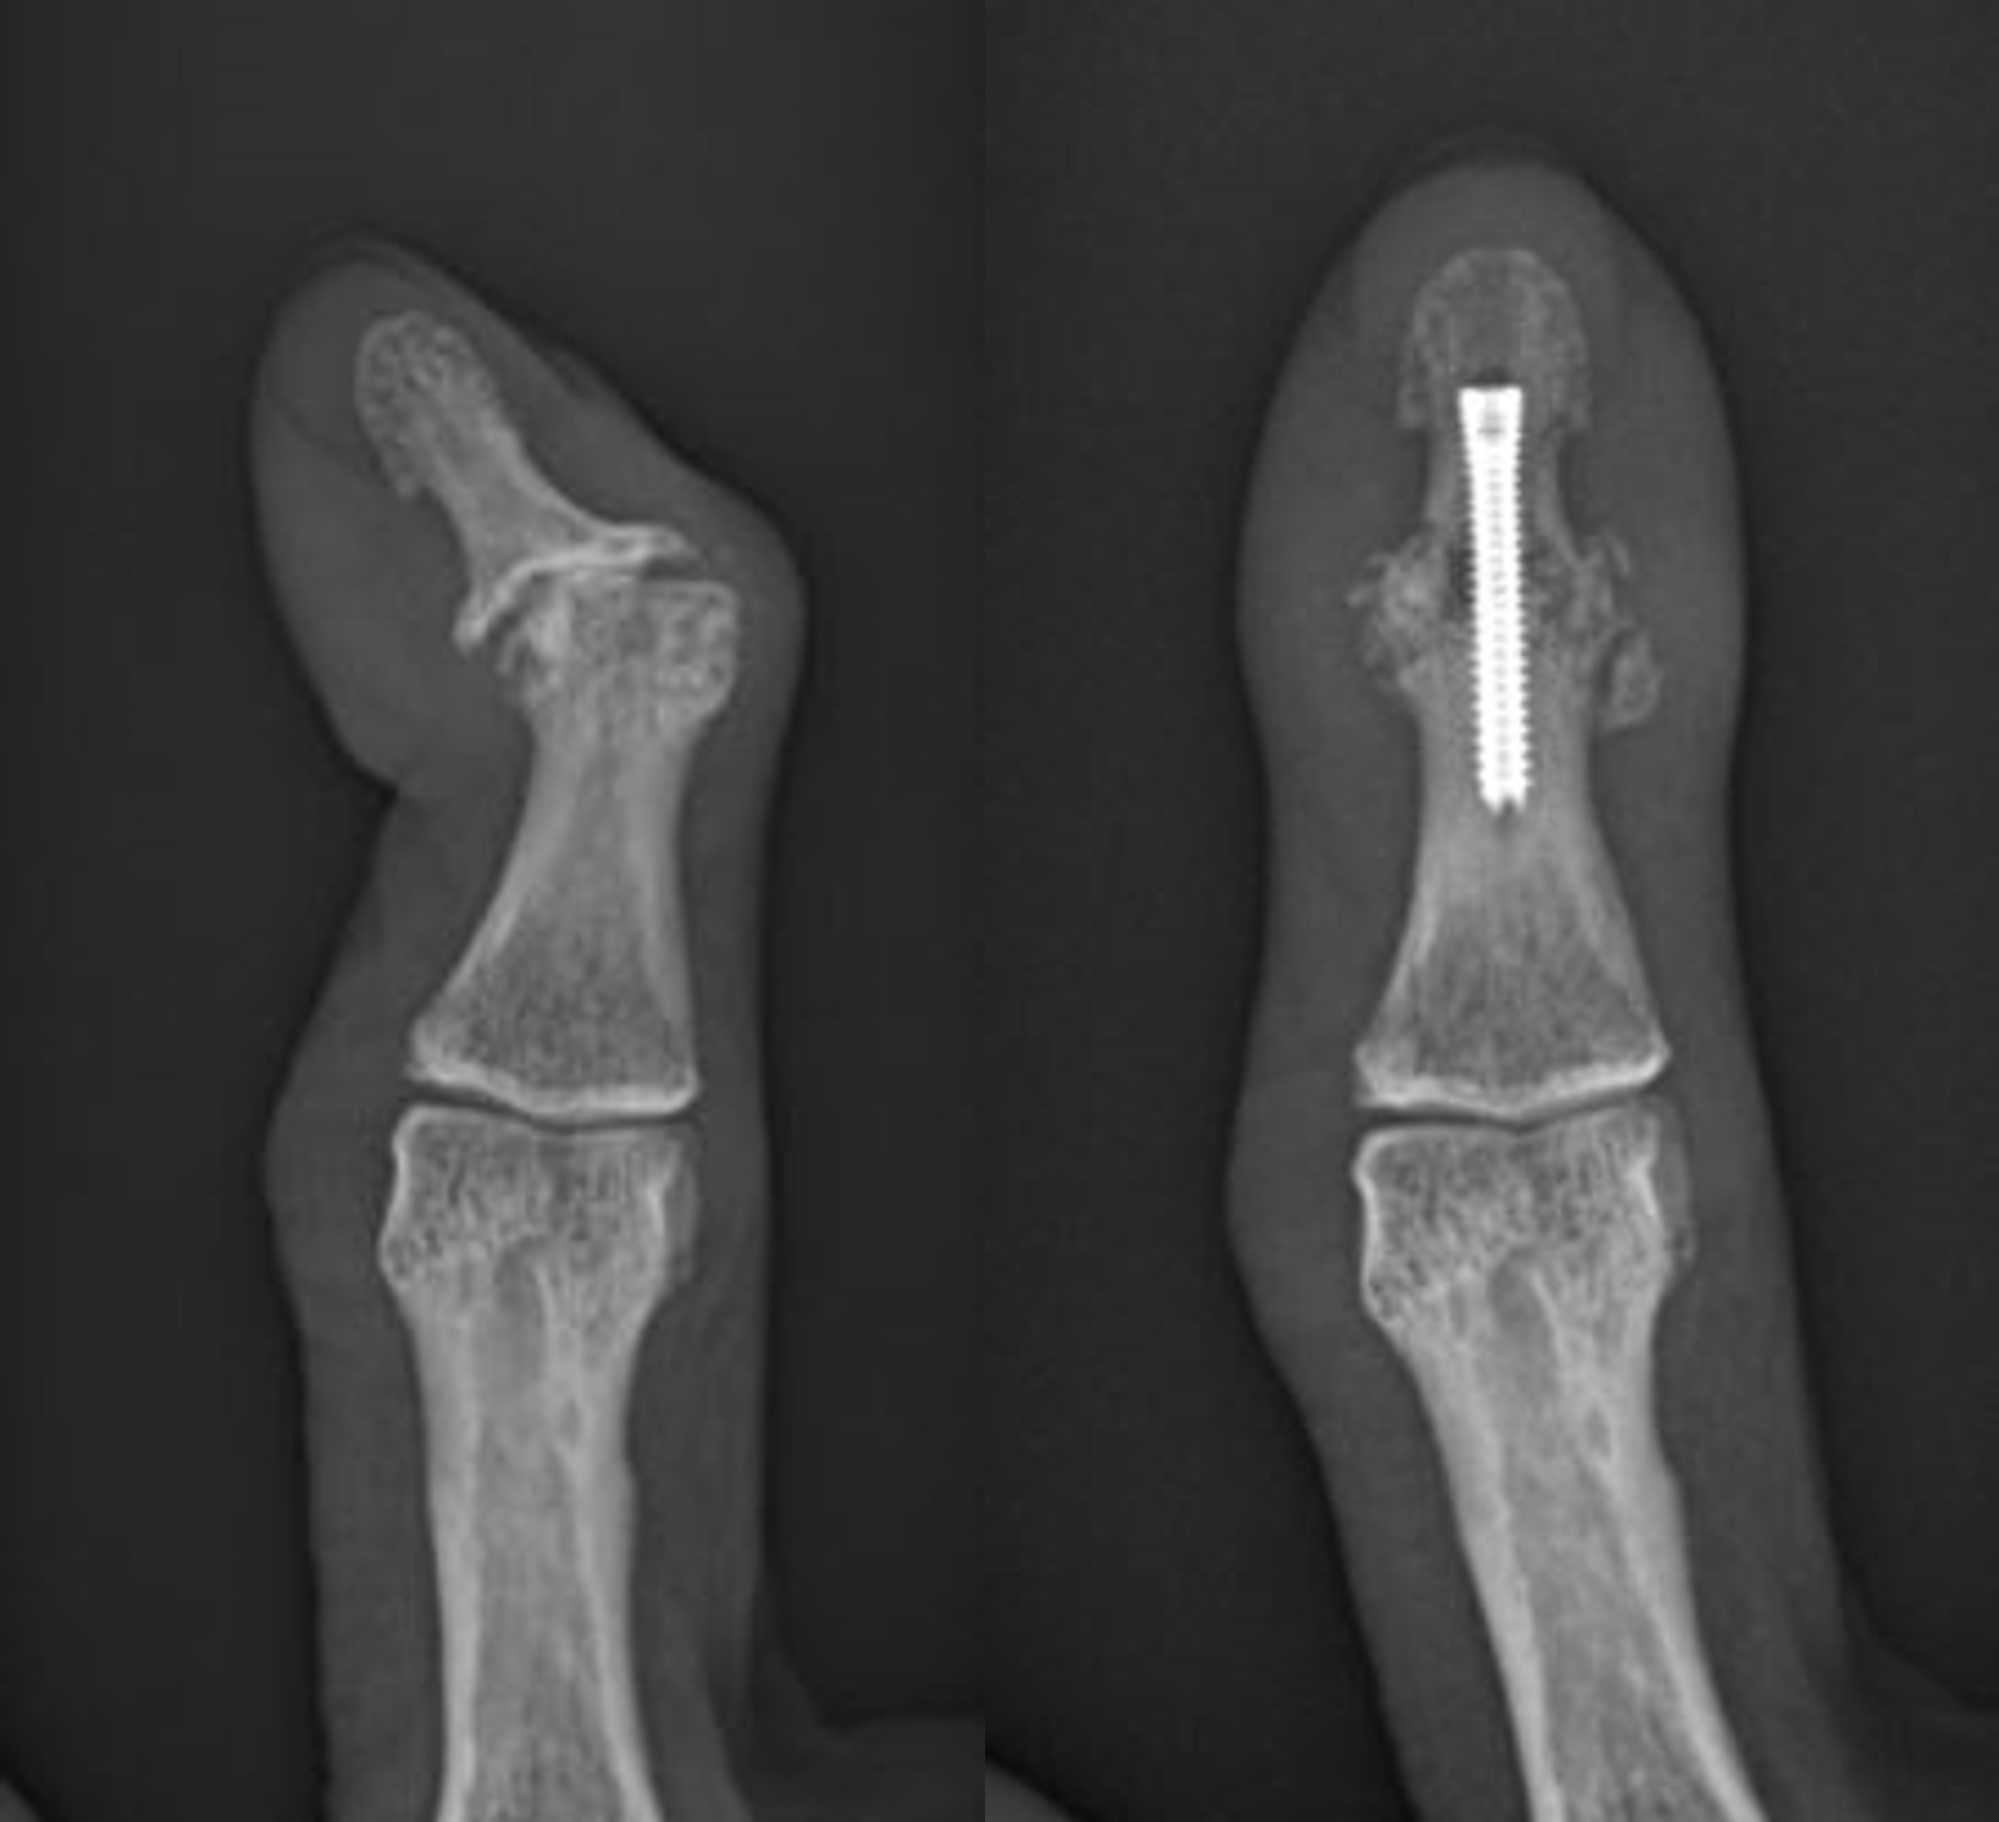

Joint Fusion

Also known as arthrodesis, joint fusion surgery uses pins, rods, or plates to join bones. This creates a single bone, dramatically reducing pain and other symptoms. Joint fusion surgery can be performed on severely arthritic joints of the fingers.